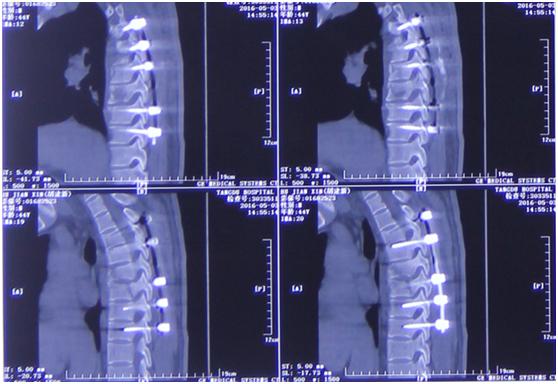

影像学资料

手术前后对比

“我们通过脊间隙制钉把脊柱完全复位了,而且对这个脊髓进行了一期的减压,减除脊髓致压物,很大程度保留脊髓功能。”李维新教授回忆“术中我们看到脊髓搏动是恢复的,而且患者脊髓复位也非常好。”